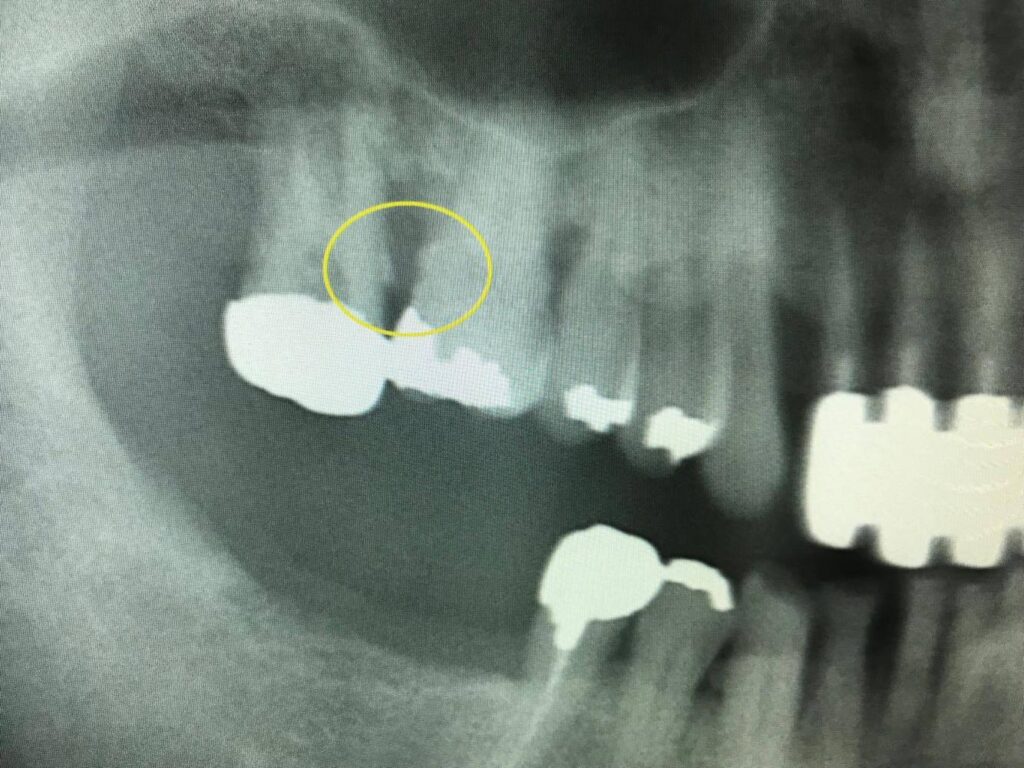

写真の黄色の円で囲まれている部分は歯石が付着し歯周病が進行している状態を示しています。

口臭・歯のぐらつき・咬合痛などの自覚症状を感じる時は重篤なことが多いので定期的な検診やレントゲン撮影を薦めています。